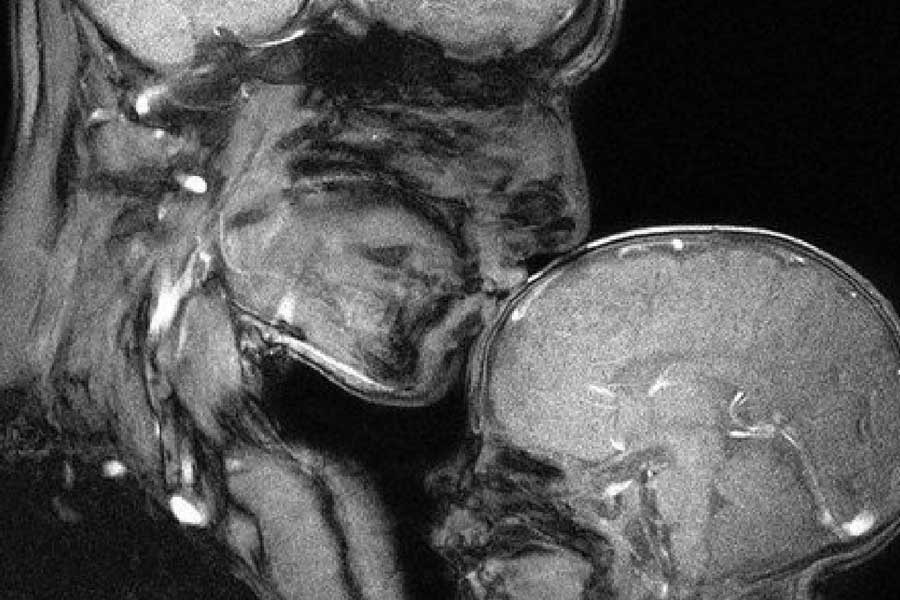

১৯৯১ সালে বিজ্ঞানচর্চার জন্য ইডা সাবেলিস নামের এক মহিলা গবেষক এবং তার প্রেমিক জুপ এমআরআই স্ক্যানারের ভিতর সঙ্গমে লিপ্ত হন। দম্পতির মিলনের সময় এমআরআই করেছিলেন নেদারল্যান্ডসের বিজ্ঞানী মেনকো ভিক্টর ভ্যান অ্যান্ডেল। সহবাসের সময় মানবদেহের ভিতরে ঠিক কী ঘটে তা ভাল ভাবে বুঝতেই এ হেন পরীক্ষার সিদ্ধান্ত নেন বিজ্ঞানীরা।

ঝুঁকিপূর্ণ এই গবেষণাটিতে এমন কিছু ছবি পাওয়া যায়, যা আগে দেখা যায়নি। এই এমআরআই-এর ছবি এবং ফলাফল যৌনমিলন সংক্রান্ত গবেষণায় একটি নতুন দিক খুলে দেয়। এই গবেষণায় প্রাপ্ত ছবি ও তথ্যের উপর ভিত্তি করেই পরবর্তী কালে বৃহত্তর বেশ কিছু গবেষণাও হয়।

ঠিক কী দেখা গিয়েছিল সেই গবেষণায়? এমআরআই স্ক্যানারের মধ্যে দম্পতির যৌনমিলনের সময় দেখা যায়, মিলনের সময় পুরুষাঙ্গ বুমেরাং-এর মতো বেঁকে যায়। অর্থাৎ ঋজু পুরুষাঙ্গও অনমনীয় নয়। বরং মিলনকালে নারীদেহে প্রবেশের পর তা বিশেষ ভাবে বেঁকে যায় কোনও রকম যন্ত্রণা ছাড়াই।

প্রাথমিক পরিকল্পনা অনুযায়ী উল্লম্ব ভাবে মিলিত হওয়ার কথা ছিল ইডা ও জুপের। কিন্তু তাতে বিশেষ কিছু বোঝা যায়নি। এর পর ইডাই পরামর্শ দেন বিভিন্ন কোণ থেকে ছবি তোলার। তাঁর পরামর্শ অনুযায়ী এমআরআই যন্ত্রের ভিতর বিভিন্ন ভঙ্গিতে মিলিত হন তাঁরা। পাশাপাশি ভাবে মিলিত হওয়ার সময় ধরা পড়ে পুরুষাঙ্গের বক্রতার বিষয়টি।

কেবল পুরুষাঙ্গই নয়, যোনিপথ এবং জরায়ু নিয়েও একাধিক তথ্য উন্মোচিত হয় এই গবেষণায়। গবেষণাটির দ্বিতীয় গুরুত্বপূর্ণ ফলাফলটি হল, যোনিপথ সরলরৈখিক নয়। তারও একটি স্বতন্ত্র বক্রতা রয়েছে। আর পুরুষাঙ্গ যোনিপথের স্বাভাবিক বক্রতা অনুযায়ী নিজেকে বাঁকিয়ে নিতে পারে।

লিওনার্দো দ্য ভিঞ্চির ১৪৯২ সালের আঁকা ছবি দেখে শারীরবিদ্যায় একটি ধারণা তৈরি হয় যে, যোনিপথ বেলনাকৃতির। পাশাপাশি এই ধারণাও তৈরি হয় যে, এক জন পুরুষের লিঙ্গ সরলরৈখিক ভাবে এক জন মহিলার যোনিতে প্রবেশ করে। আবার সরাসরি বেরিয়ে আসে। এই গবেষণায় পাঁচ শতাব্দী প্রাচীন সেই ধারণা ভেঙে যায়।